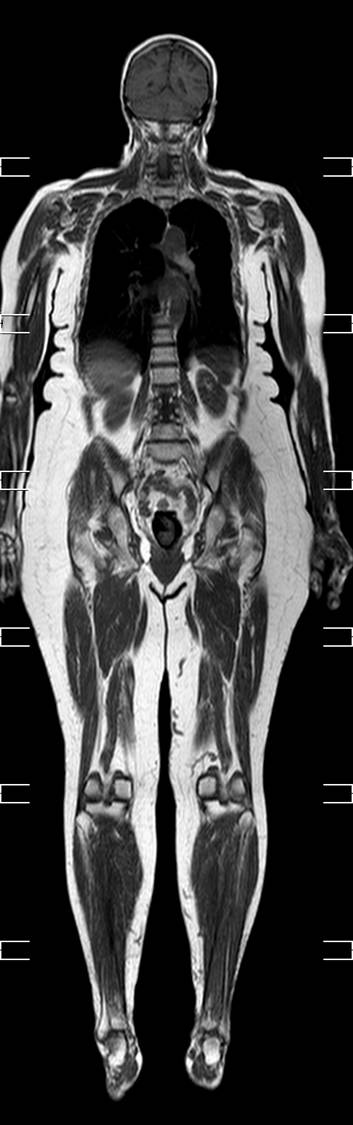

MR-skanner, helkrops

Helkrops MR-skanning. Det tager under 30 minutter at nå fra top til tå 2 gange. Man laver en fedtsupprimeret T2-vægtet skanning , hvor man får fremstillet, hvor der er vand i kroppen.

Her ses en T1-vægtet skanning, hvor anatomien er bedre fremstillet.